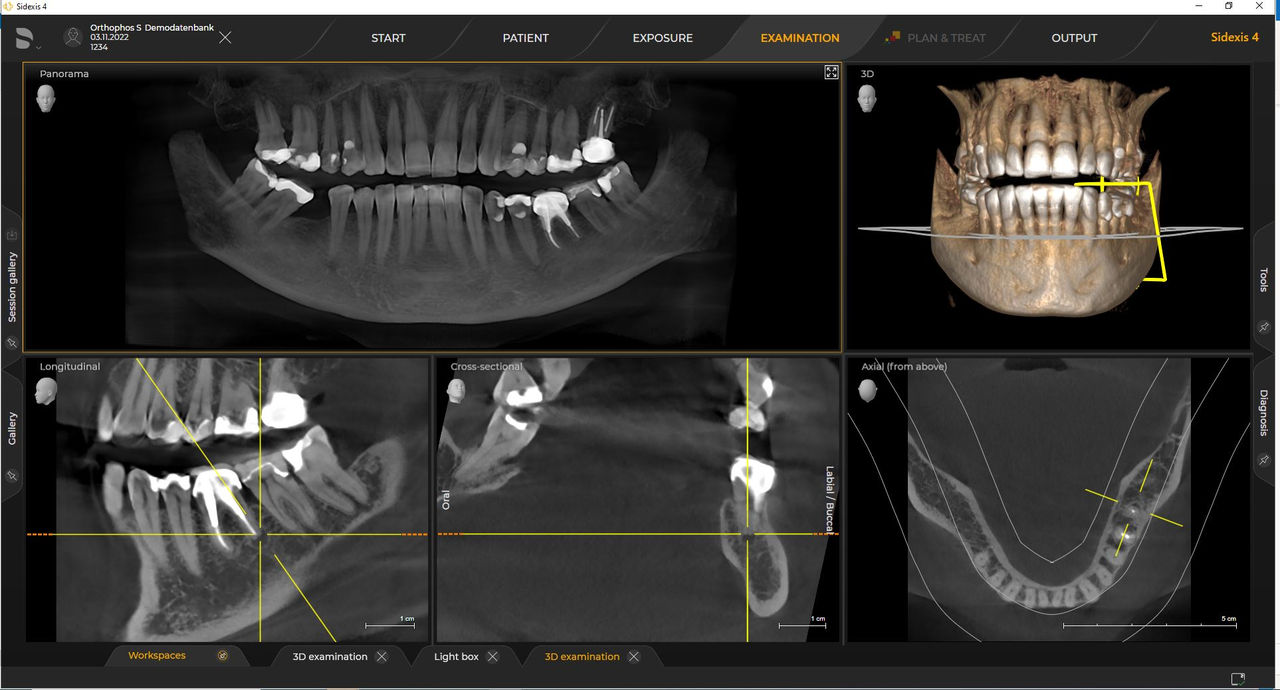

Las unidades de radiología de Dentsply Sirona funcionan exclusivamente con Sidexis 4. Sin embargo, la migración de datos de Sidexis XG a Sidexis 4 es muy fácil. Sidexis 4 permite una experiencia digital completa con las últimas herramientas

Con el modo de dosis baja inteligente 3D, obtiene imágenes 3D en el rango de dosis de una imagen radiológica 2D. En el modo HD (hasta 1400), las imágenes individuales se obtienen durante una única rotación y se convierten en un volumen 3D con hasta 80 μm para imágenes de bajo ruido en alta resolución.

Una amplia gama de tamaños de volumen para satisfacer sus diversas necesidades clínicas y de diagnóstico, desde Ø 5 x 5,5 cm hasta Ø 11 x 10 cm